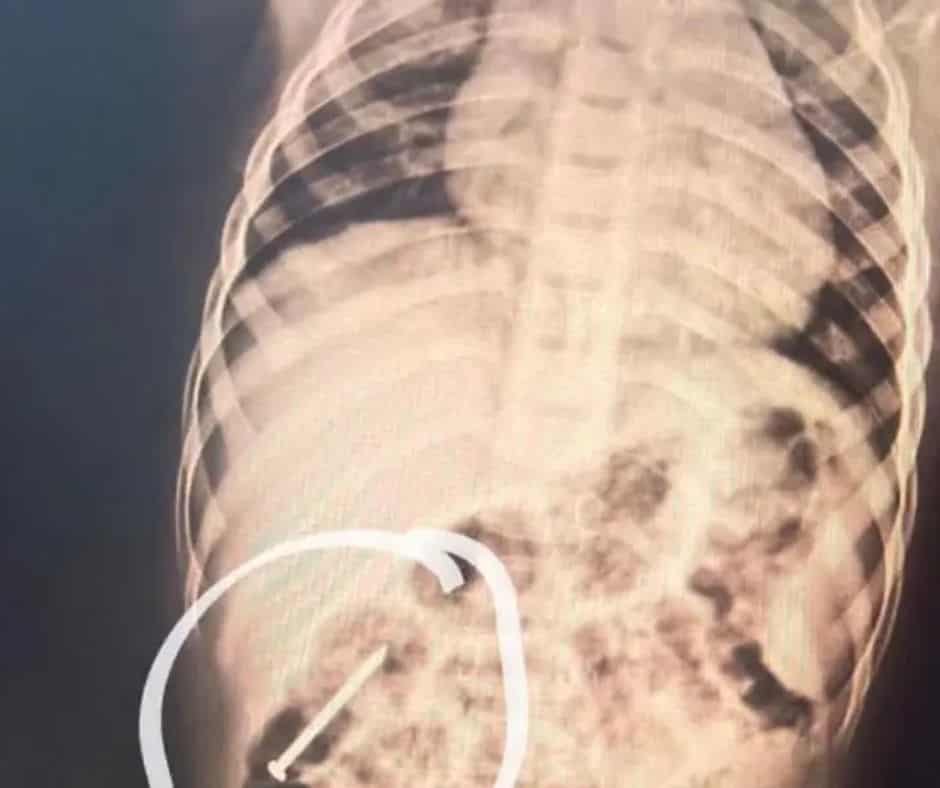

Um menino de apenas 3 anos está internado no Hospital do Juruá, em Cruzeiro do Sul, desde a última quarta-feira (14), após ingerir um prego que acabou ficando retido no intestino. A criança é natural do município de Ipixuna, no interior do Amazonas, e foi transferida para o Acre cerca de seis dias depois do ocorrido.

Ao chegar à unidade hospitalar, o paciente foi submetido a exames clínicos e de imagem e permanece sob vigilância médica contínua. O atendimento envolve profissionais das áreas de pediatria, endoscopia e cirurgia, que acompanham de perto a evolução do caso. Até o momento, não houve necessidade de intervenção cirúrgica.

Segundo a equipe médica, o estado de saúde do menino é considerado estável. Os exames realizados diariamente indicam que o objeto está avançando pelo intestino de forma natural, o que permite a adoção de uma conduta conservadora, baseada apenas em observação.